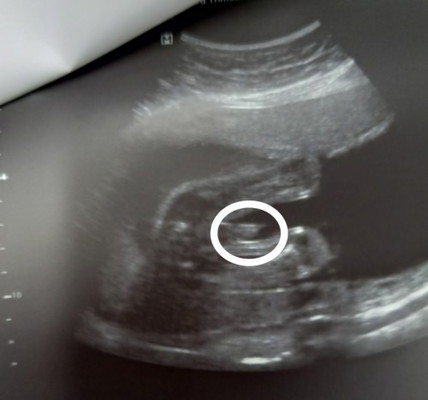

Hi mga momshie, sabi ng sonographer ko boy daw kasi may lawit. Sana di na magbago kc gusto q talaga ng baby boy. Ano po kaya sa tingin nyo mga momshie?#1stimemom #firstbaby

it's a boy! kapag nakita nyong may lawit sa pagitan ng legs, pototoy po yun 😅 tapos kung ayaw magpakita ng gender, kadalasan baby girl, matik yun 😅

Sure na boy yan mommy. Ganyang ganyan lumabas sa ultrasound ko haha

Yes po. Baby boy. Ganyan din sa akin. Boy naman din lumabas

baby boy sis ganyan dun sakin sa ultrasound baby boy po

positive baby boy po ganyan din kay baby non